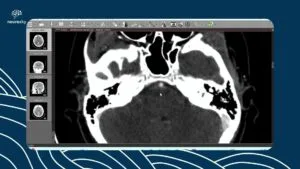

- Avaliação por Imagem: Importância das técnicas de ressonância magnética (RM) na identificação de alterações no hipocampo.

- Características Imagens: Discussão sobre as características típicas observadas nas imagens que auxiliam na diferenciação de outras patologias.